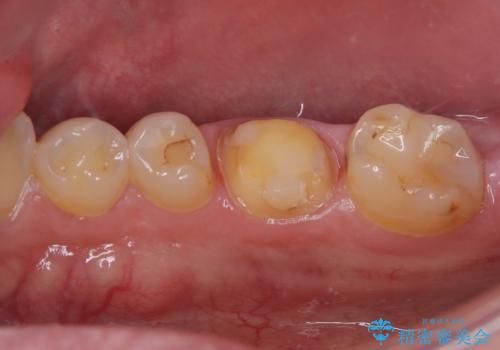

拡大鏡視野下で、セラミックの詰め物(セラミックインレー)、虫歯の除去を行い、オールセラミッククラウンに適した形に整えました。

歯と歯茎の間に圧排糸と言われる糸を入れてシリコーン印象材にて型どりをしました。